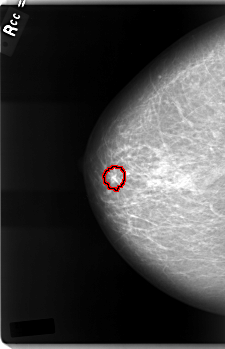

C_0003_1.RIGHT_CC

FILE: C_0003_1.RIGHT_CC.OVERLAY

TOTAL_ABNORMALITIES 1

ABNORMALITY 1

LESION_TYPE MASS SHAPE IRREGULAR MARGINS SPICULATED

ASSESSMENT 5

SUBTLETY 5

PATHOLOGY MALIGNANT

TOTAL_OUTLINES 1

BOUNDARY